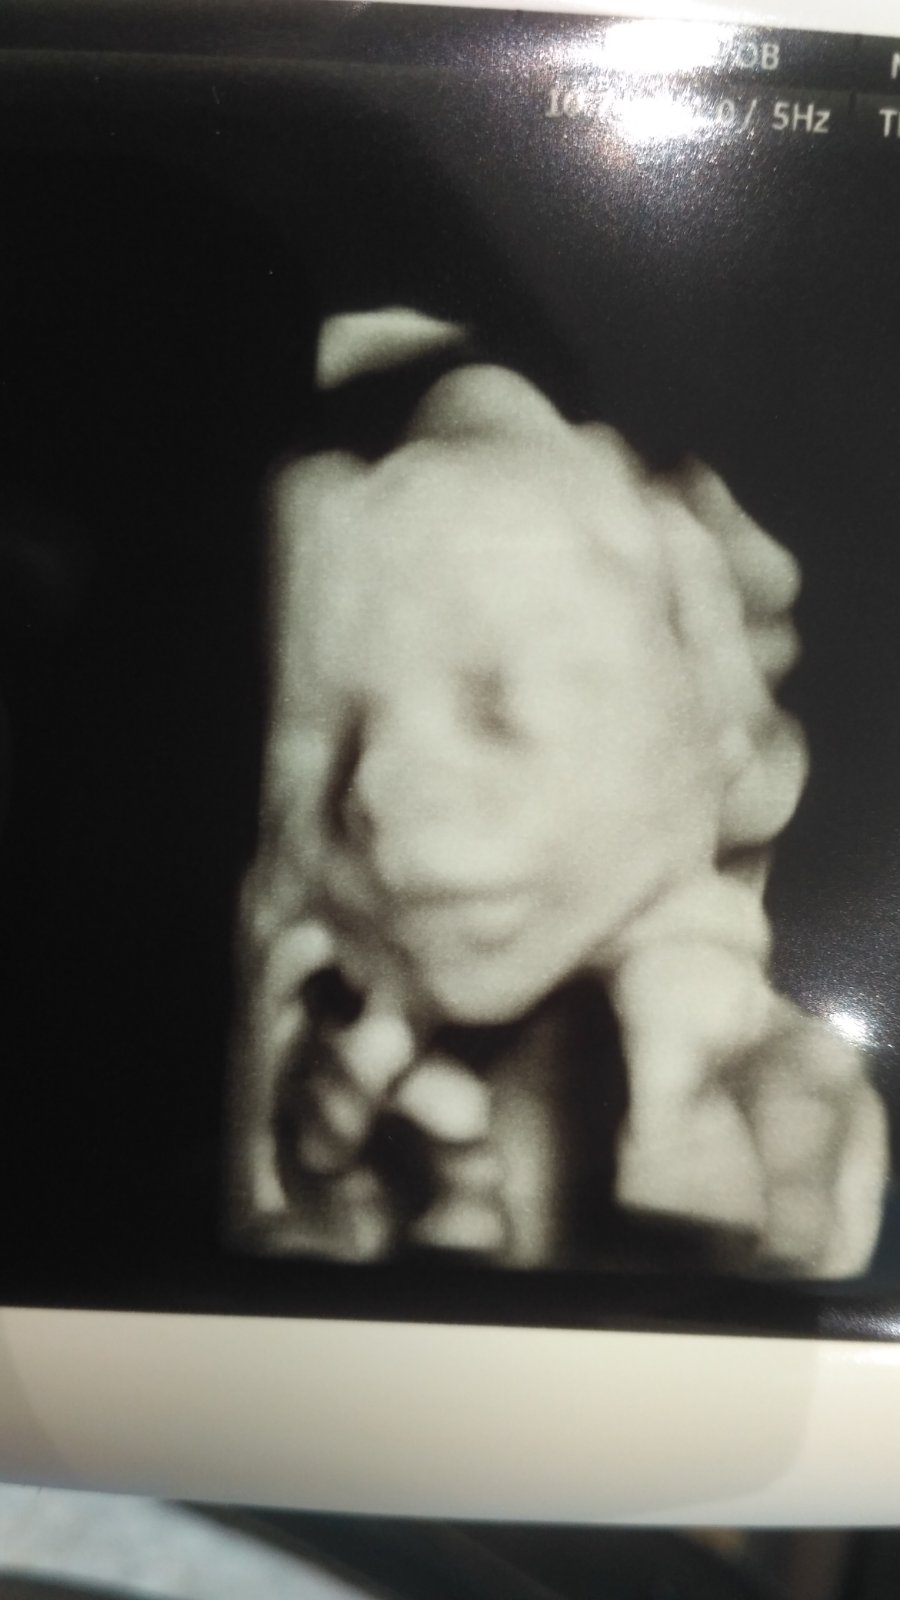

@susangha

@susanne08

@zuzumajko tak babenky mám za sebou usg a budeme mať na 99 % dievčatko 😍 veľmi ma to potešilo aj keď mi to bolo viacmenej jedno 😘 mala je v poriadku a zdravá a to je základ aj keď ja som prácou zdeformovaná a kým ju nebudem mať v náručí tak nebudem spokojná 🙈

@zuzu8511 juch aka je rozkosnicka 🥰🥰 preco mne nespravil nas gyndos na morfe taku krasnu fotecku princeznej?